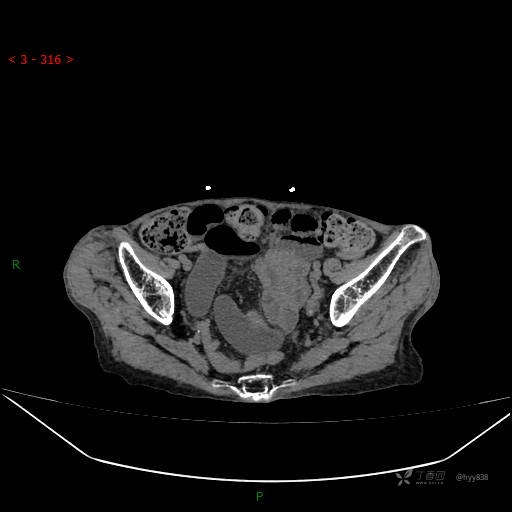

腹部CT平扫